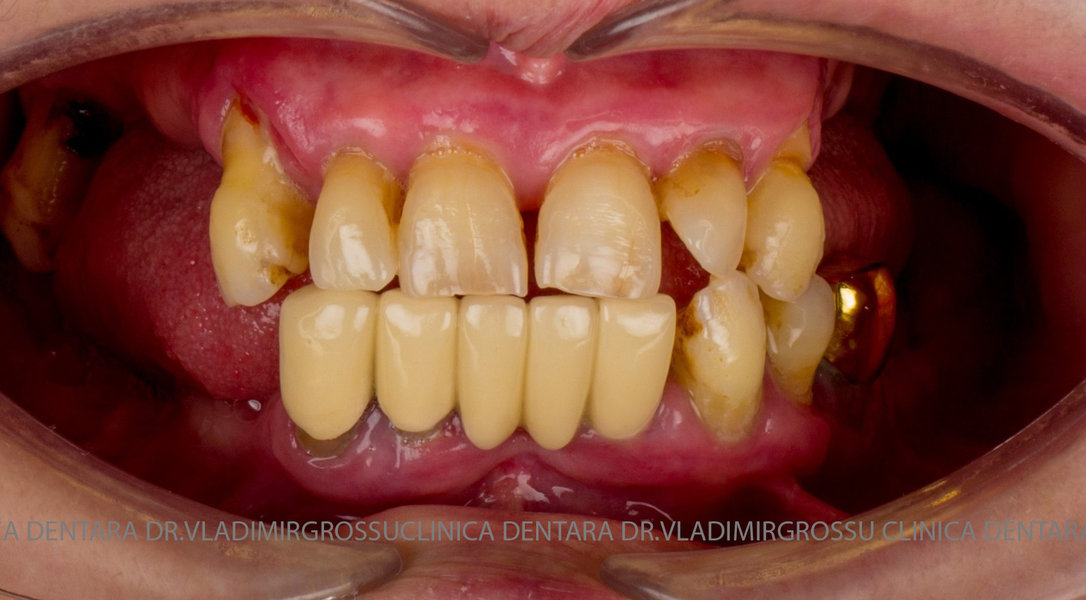

Cazuri clinice conceptul All-on-6